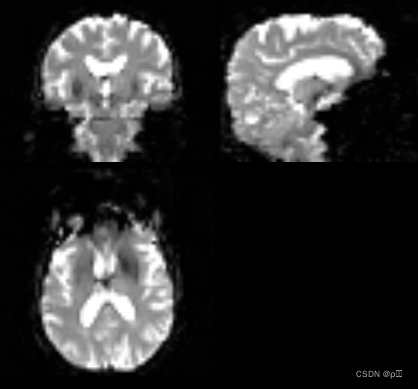

静息态fMRI是在被试者处于放松或静息状态下记录大脑活动的一种技术。在静息态fMRI中,被试者不需要执行特定的任务,但大脑仍然表现出自发的神经活动。通过观察大脑不同区域之间的时间相关性和功能连接模式,可以研究大脑的功能网络、脑区之间的相互关系以及其在健康和疾病状态下的变化。静息态fMRI可以揭示大脑内在的功能结构和组织,并用于研究大脑的连通性、功能网络和脑网络的异常。下图为静息态fMRI的轴状位、矢状位、冠状位图。